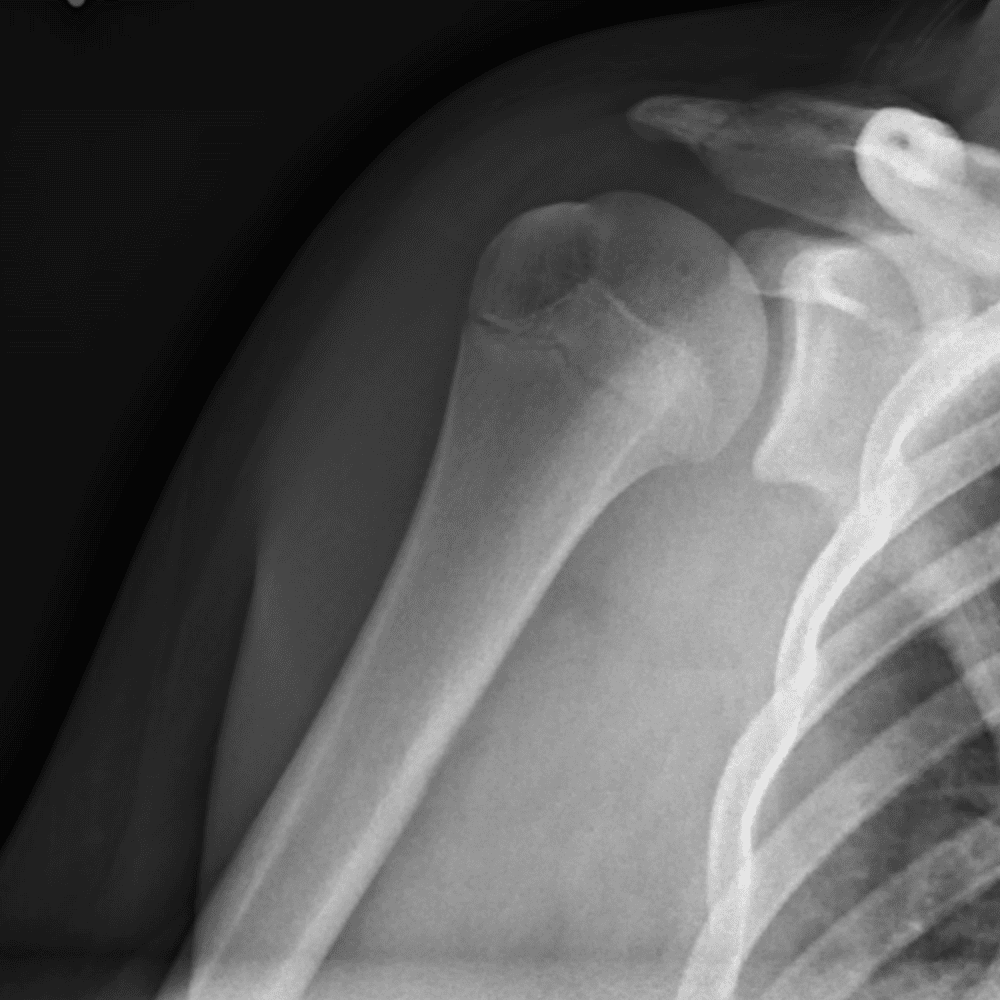

Simuliert den Dienst durch subtile oder schwierige Fälle und einige Normalbefunde.

30 Fälle